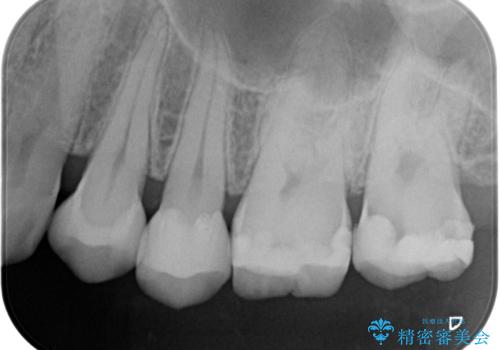

- 矯正前の患者様です。検査をしたところ虫歯が見られたので拡大鏡下で虫歯を取り除き

e-maxインレーで治療を行いました。

虫歯が多数ありましたのでまずは2本虫歯治療を行いました。